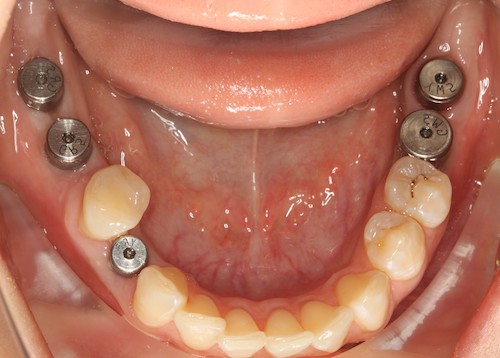

И в случае потери самых последних зубов и невозможности постановки моста, имплантация это единственный способ восстановить зубы в этом отделе в несъемном виде.

Рис.8 Концевые дефекты.Поставлены импланты.Мост поставить нельзя.